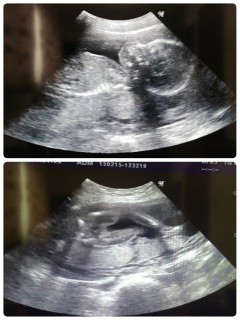

ぼんやりしか顔が映らずw 9年ぶりに授かりました第二子です! 性別はまだ不明(* >ω<)

BPD→52.3mm

FL→35.1mm

先生がまだ体重は出さないと言うので 推定体重は不明ですが 週数通りの順調な成長だと言われました!

子宮頸管無力症で13wで入院&手術して やっと22wまできましたヽ(^◇^*)/ 縛ったにも関わらず 頸管が短すぎて産まれるまで退院できませんが 順調な成長に励まされて 寝たきりの入院生活頑張ってます!